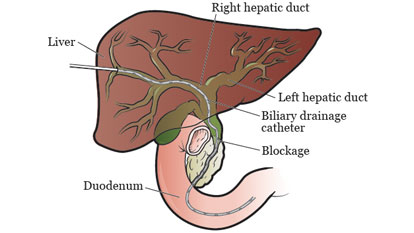

Biliary Drainage Procedures

Biliary drainage procedures are minimally invasive interventions used to relieve obstruction in the bile ducts, which can occur...